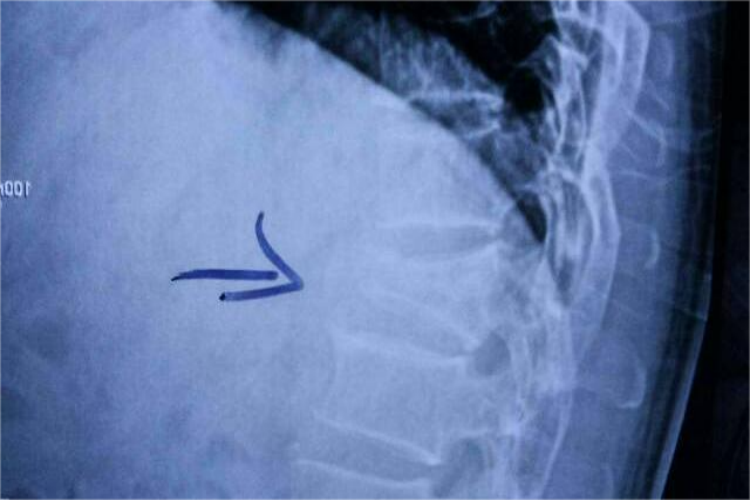

t12胸椎压缩性骨折X线检查侧位片上,可见椎体前上方压缩成楔形;或整个椎体压扁,或呈“鱼尾样”,椎体前缘连线可中断。在正位片上可见椎体变扁或一侧呈楔形。同时患者可有明显的腰部疼痛,不能站立行走,翻身困难等症状。